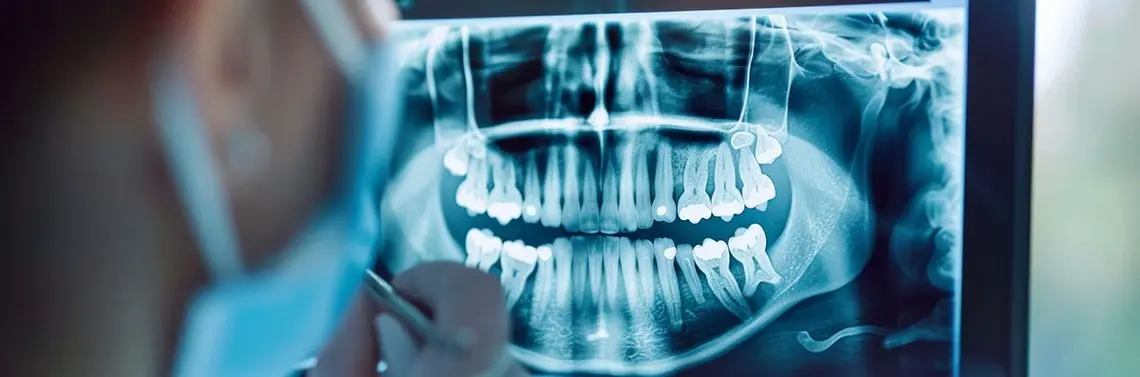

45-letni pacjent zgłosił się do poradni protetyki stomatologicznej w celu oceny oraz odbudowy zębów w żuchwie. Zlecono wykonanie badania TK żuchwy – badania OPG (zdj. 1A–J).

Na podstawie badania klinicznego oraz badań obrazowych stwierdzono znaczne zniszczenie twardych tkanek zębów oraz zmiany w okolicy okołowierzchołkowej zębów 36, 37, zajęcie furkacji zęba 37 oraz obecność zatrzymanego zęba 38.